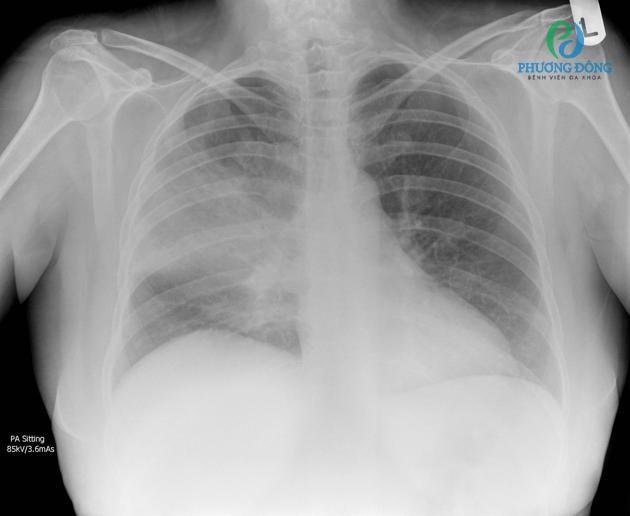

Chụp X-quang phổi là một phương pháp chẩn đoán hình ảnh phổi phổ biến và là chỉ định thông thường của bác sĩ khi muốn kiểm tra sức khỏe và sàng lọc các bệnh về phổi. Phương pháp này có thể cho kết quả trong thời gian ngắn và cung cấp những thông tin liên quan đến các bệnh lý phổi và lồng ngực, từ đó giúp các bác sĩ đưa ra được chẩn đoán, phác đồ điều trị và chăm sóc thích hợp cho bệnh nhân.

Chụp X-quang phổi là một phương pháp chẩn đoán hình ảnh phổi phổ biếnChụp X-quang phổi là một phương pháp chẩn đoán hình ảnh phổi phổ biến